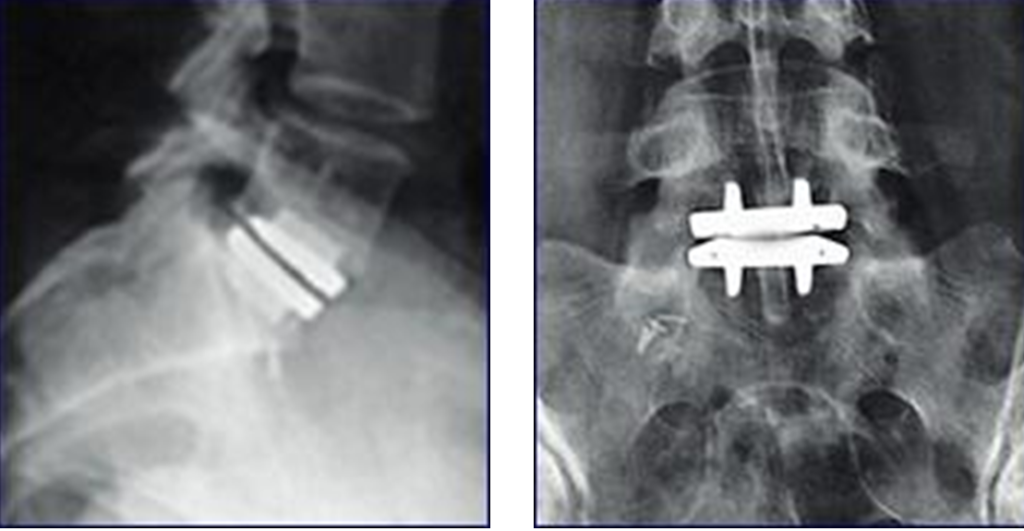

From www.researchgate.net

Lateral radiograph showing Charité lumbar disc replacement L5/S1 Disc Replacement Radiology Cervical total disc replacement (ctdr) was developed as an alternative treatment, in order to avoid drawbacks of acdf by replacing the degenerative discs and. Disc arthroplasty is the replacement of a painful pathological intervertebral disc by a prosthesis, which, unlike spinal fixation, has the. The purpose of this article is to illustrate common postoperative complications and their imaging appearances after. Disc Replacement Radiology.